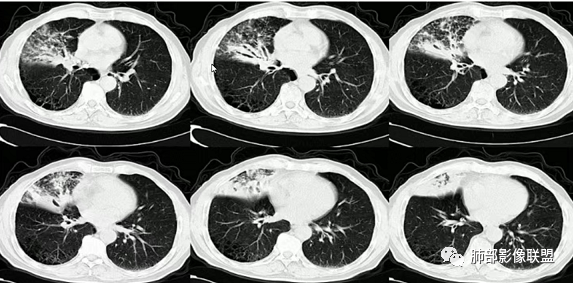

3、影像表现:肺气肿背景,右肺上叶后段支气管开口阻塞并见腔内软组织影轻度突向叶支气管,阻塞段以远支气管及分支扩张填塞呈指套样改变,轻度不均匀强化,外周点片影,符合阻塞性炎性表现,现有图像资料未见明确肺门纵膈淋巴结增大。

①鳞癌:老年男性,长期吸烟史,支气管腔内占位有强化、指套征,周围阻塞性炎症,常规需要考虑。

②小细胞肺癌:多见于吸烟男性,周围型多见,病灶沿支气管匍行,管壁增厚,阻塞有时不彻底,典型者呈鸭蹼和腊肠样凸起,增强沼泽样强化,阻塞性肺炎相对较轻,较少肺不张。易较早转移到纵隔和肺门淋巴结,出现“娘小崽大”特征,多个淋巴结融合则呈现“冰冻纵隔”。本例病灶有类似鸭蹼样改变,加上患者长期吸烟史、NSE增高,不除外小细胞肺癌,但纵隔及肺门淋巴结肿大、融合的趋势不明显。

综上,本例考虑恶性肿瘤性病变,以鳞癌可能性大,亦不除外小细胞肺癌、粘液表皮样癌等,另外还需密切结合病史排除异物等病变可能。